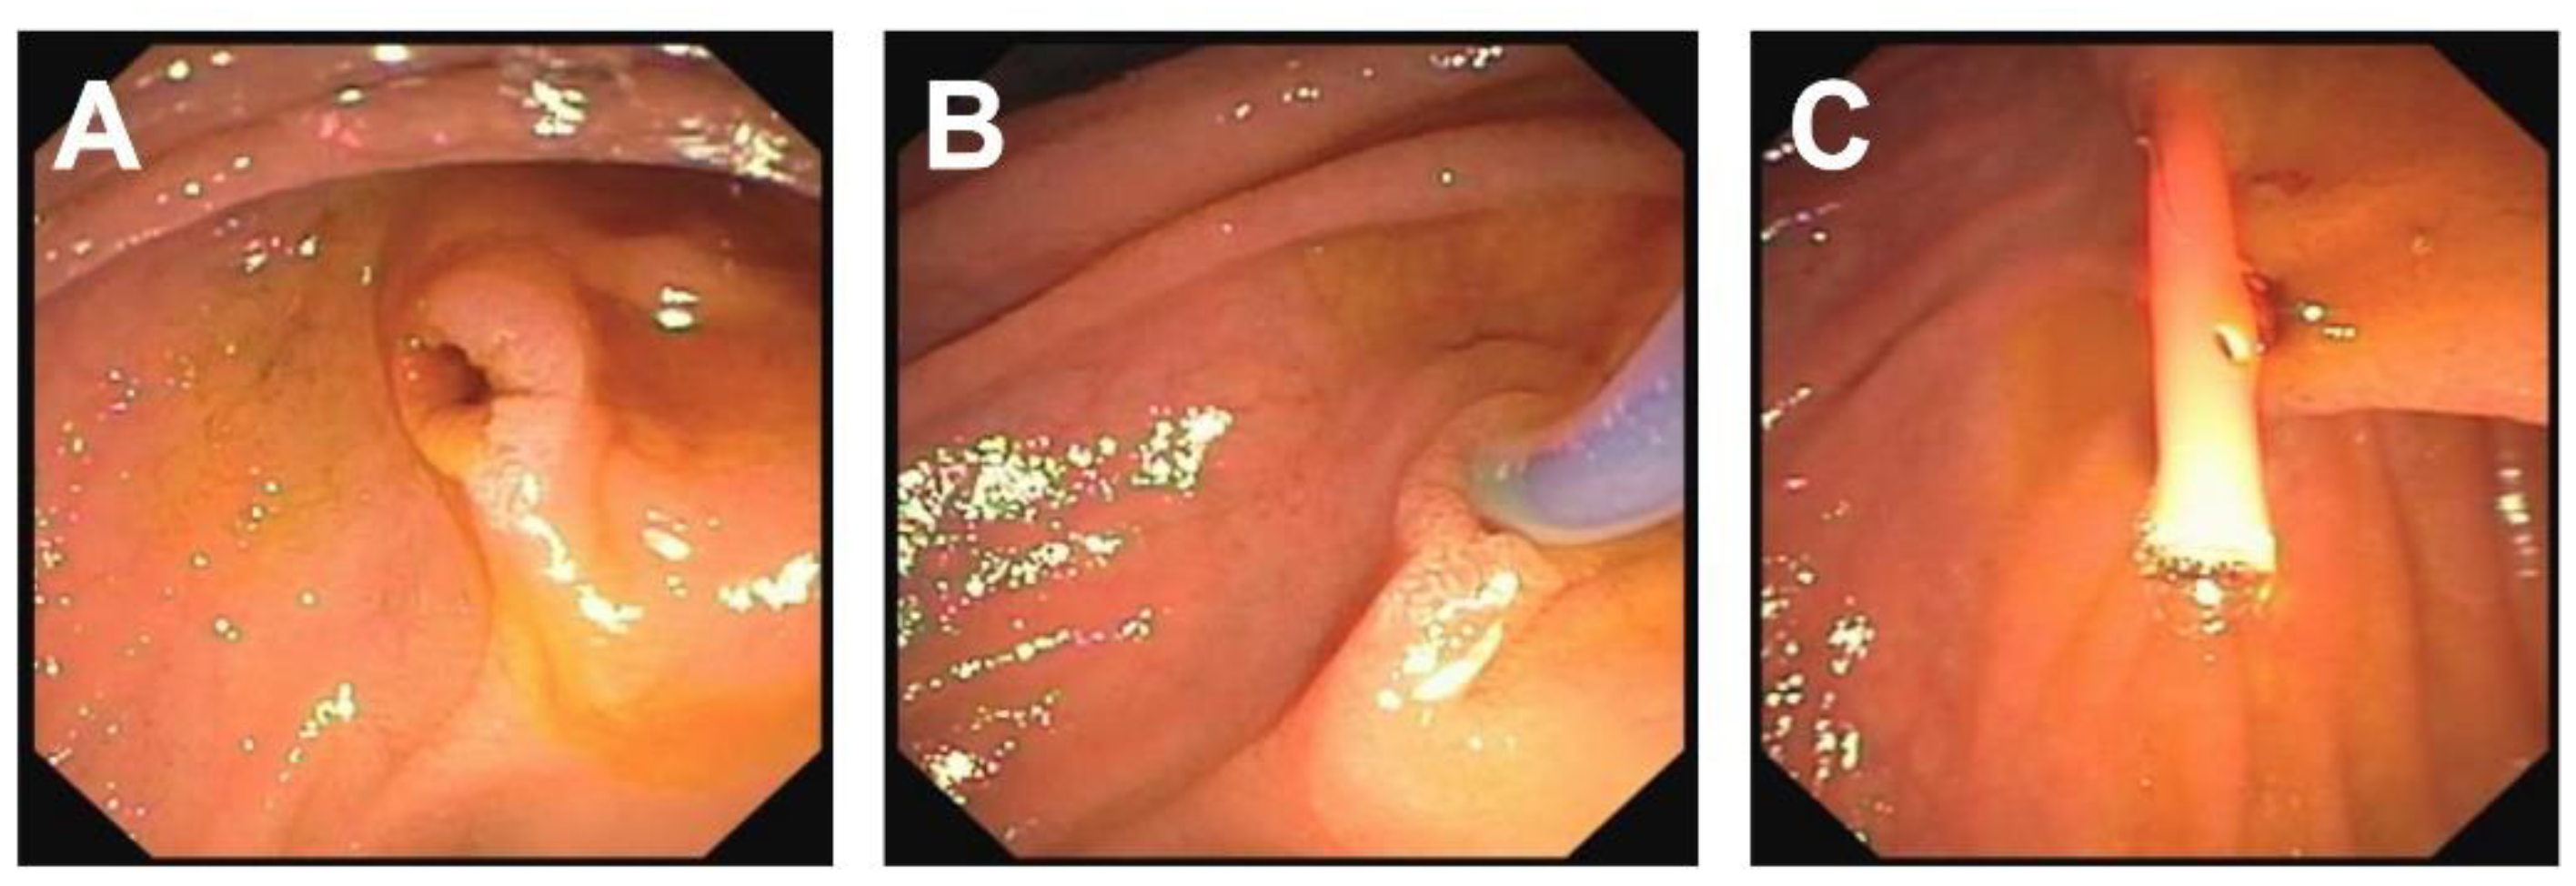

| Initial Management | Laparotomy, suture of the pancreatic head, distal pancreato-jejunostomy (Roux Y) | ERCP—complete dissection of the pancreas, Laparotomy, Jejunal repair, suture of the pancreatic head, distal pancreato-gastrostomy | ERCP—stenting of the ruptured pancreatic duct with 5 Ch pigtail drainage | ERCP unsuccessful, stenting of ruptured pancreatic duct not possible; chest drain (left side) |

| Management of complications | Anticoagulant therapy | - | Transgastric punction and drainage of pseudocyst with double-pig tail drain Ch 7, spontaneous dislocation of pig tail Antibiotic therapy Persistent fistula of the ruptured pancreatic duct, recurrent stenting (2 times), removal of stent after 5 months | Transgastric punction and drainage of pseudocyst with double-pig tail Ch 7, spontaneous dislocation of pig tail Antifungal therapy |